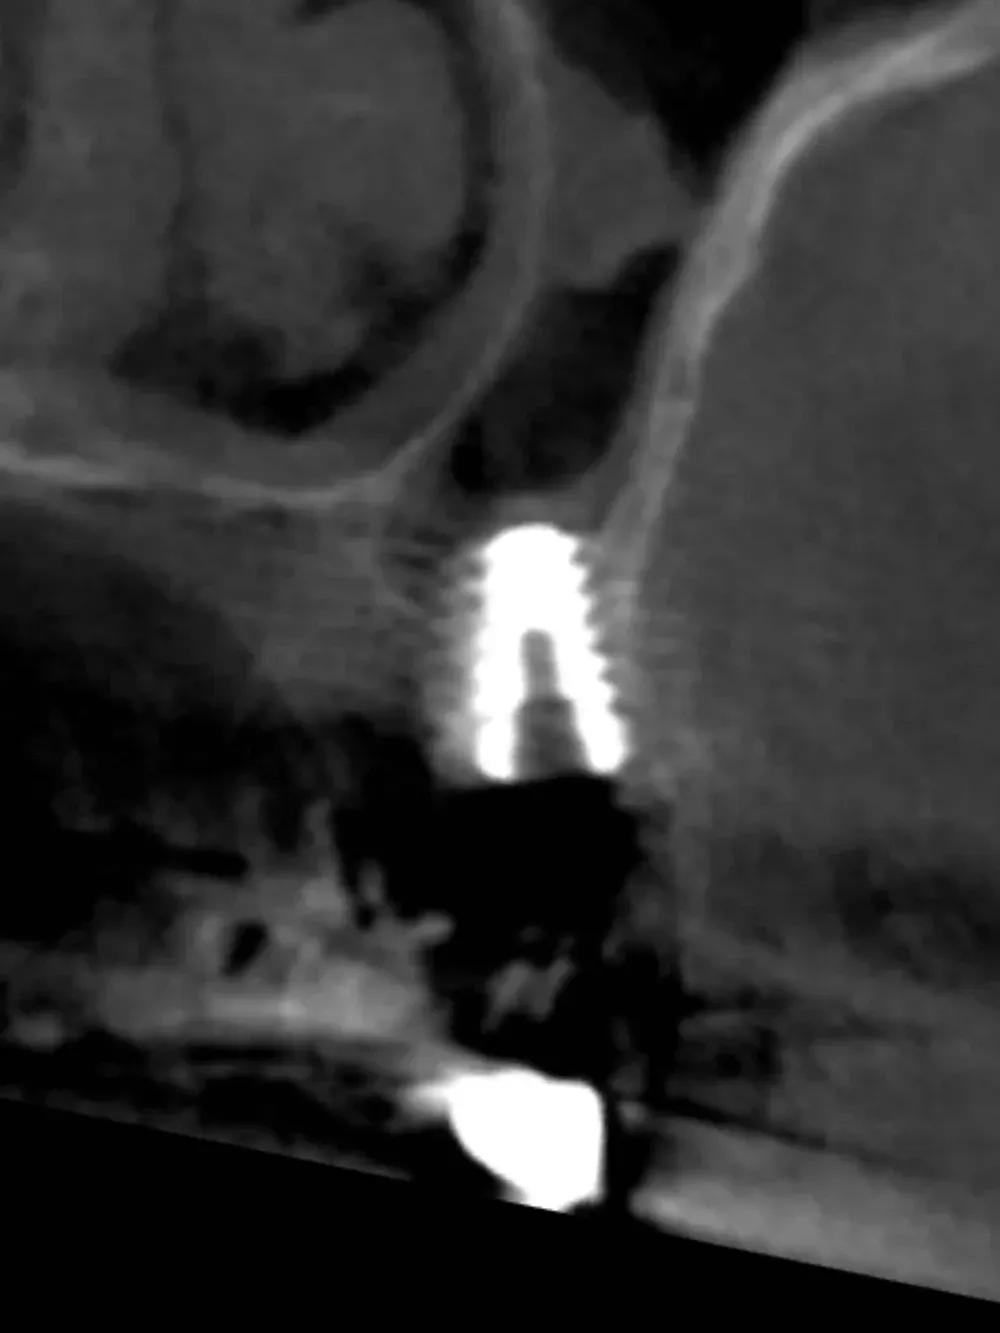

La CBCT intraoperatoria ha confermato la corretta posizione tridimensionale degli espansori e il raggiungimento della corticale del pavimento del seno in zona 2.5. In caso di dubbi sulla posizione e nel corso di interventi delicati come questo, questo ausilio strumentale è di fondamentale importanza. Ma non è sempre necessaria. L’esposizione, per quanto contenuta, dev’essere sempre ridotta al minimo, compatibilmente con la sicurezza chirurgica.

Sezione espansore sito 2.4

CBCT Post-op: Impianto in posizione 2.4 infracrestale che ha raggiunto la posizione di ingaggio corticale corretta